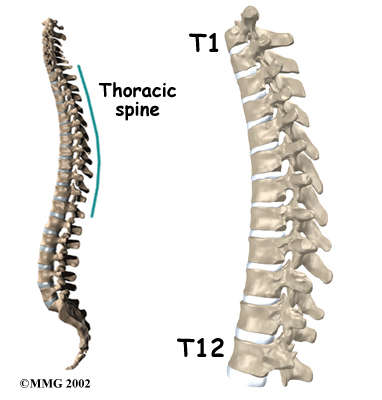

The human spine is made of 24 spinal bones, called vertebrae. Vertebrae are stacked on top of one another to create the spinal column. The spinal column gives the body its form. It is the body's main upright support.

The main section of each vertebra is a large, round structure called a vertebral body.

Compression fractures cause this section of bone to collapse. When the fracture is due to osteoporosis, it usually occurs in the lower part of the thoracic spine, near the bottom of the rib cage.

A bony ring attaches to the back of each vertebral body. When the vertebrae are stacked on one another, the bony rings form a hollow tube. This tube, or canal, surrounds the spinal cord. The spinal cord is like a long wire made of millions of nerve fibers. Just as the skull protects the brain, the bones of the spinal column protect the spinal cord.